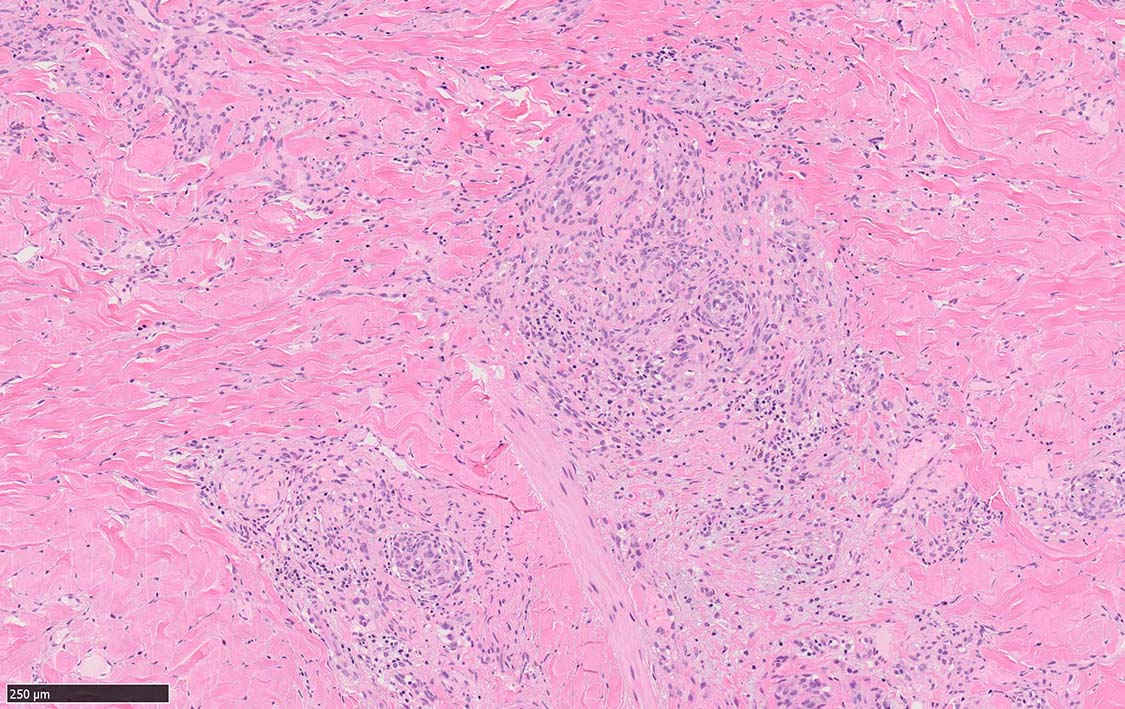

局面状病変の病理

病変は真皮から皮下脂肪織に及ぶようになり, 血管内皮様細胞による新生管腔の増加と拡張, 浮腫が著明になる. 赤血球漏出やヘモジデリン貪食細胞もめだつようになる.

膠原線維間に紡錘形細胞が増生してくる.